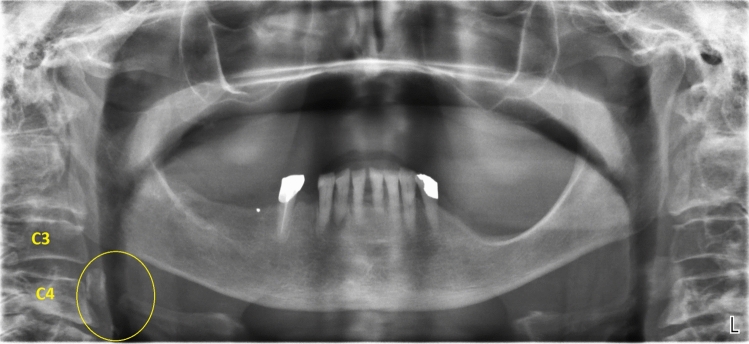

The PRs were observed in full-screen mode. Overexposed images or calcifications that had low radiopacity were clarified or zoomed in using software tools. If a patient had multiple PRs, only one of them was included in the study, choosing the one with the best image quality. Radiographs that were distorted because of the subjects’ movements during the exposure and those that did not include C3 and C4 vertebrae were excluded. Images with an ambiguous diagnosis due to superimposed structures or lack of clarity, were discarded as well. PRs that did not display the stylohyoid ligament complex in good image quality or in which the origin of the styloid process from the lower part of the temporal bone was hidden by the shadows of the base of the skull, were not included in the study. The presence of radiolucent lesions and radiopacities compatible with mineralization were studied, as well as their unilateral or bilateral characteristics. The patient’s age and sex were recorded for each radiograph reviewed.

(a) Carotid artery calcifications

Since their presence was first reported in 1981 [1], radiopacities in the lateral parts of the neck, have received more attention. In fact, in digital panoramic radiographs, the area situated inferiorly and laterally to the hyoid bone, corresponds to the bifurcation of the internal and external carotid arteries, which is exactly where carotid artery calcifications (CAC) are often present. In panoramic radiographs, the bifurcation of the internal and external carotids is situated around the intervertebral discs C3 and C4 or at a 45° to the jaw angle [2, 3]. For this reason, nodular and heterogeneous radiopacities found in these areas may be identified as atherosclerotic calcifications of the carotid arteries. Nonetheless, false-positive results are still possible, because other radiopaque structures are present in these areas, like the triticeous cartilage [4].

In the present study, irregular and heterogeneous radiopacities, occurring at the bifurcation of the carotid arteries, at the level of C3–C4, adjacent to the cervical spine and hyoid bone, were diagnosed as carotid artery calcifications (CAC).